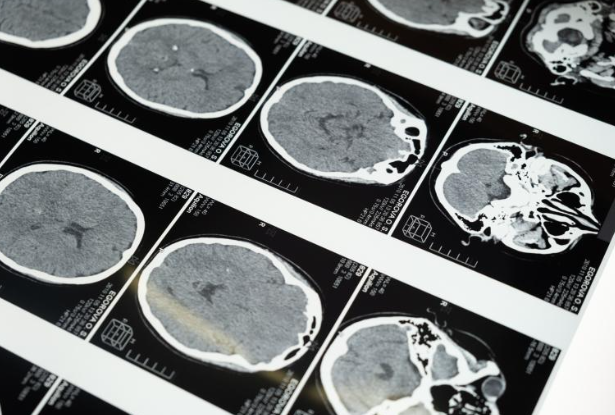

두개내 고혈압 치료

- 증상: 아침에 심해지는 두통, 시력 문제, 메스꺼움, 구토, 때로는 의식 혼란이나 상실을 포함합니다.

- 원인: 뇌척수액의 과도한 생산이나 흐름 장애, 뇌 내 종양, 출혈 등에 의해 발생할 수 있습니다.

- 관리 방법: 이뇨제와 같은 약물 치료와 뇌척수액을 다른 부위로 우회시키는 수술이 필요할 수 있습니다. 근본적인 원인의 치료도 중요합니다.

뇌종양 진단 및 치료

- 증상: 아침에 심해지는 두통, 구토, 시력 문제, 인지 및 행동 변화, 발작 등이 발생할 수 있습니다. 두통의 성격은 점진적으로 악화되며, 야간 또는 아침에 더 심해질 수 있습니다.

- 원인: 뇌종양은 다양한 유형의 종양에 의해 발생하며, 정확한 원인은 대부분의 경우 명확하지 않습니다.

- 관리 방법: 수술, 방사선 치료, 화학 치료 등 종양의 종류와 단계에 따라 다양한 치료 옵션이 있습니다. 치료 계획은 개별 환자의 상태에 따라 결정됩니다.